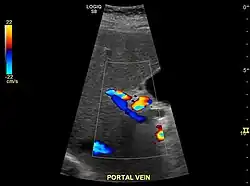

Caudate lobe hypertrophy on ultrasound due to cirrhosis

Hepatofugal (non-forward) flow in portal vein

Imaging

Ultrasound is routinely used in the evaluation of cirrhosis.[45] It may show a small and shrunken liver in advanced disease. On ultrasound, there is increased echogenicity with irregular appearing areas.[64] Other suggestive findings are an enlarged caudate lobe, liver surface nodularity[65] widening of the fissures and enlargement of the spleen.[66] An enlarged spleen, which normally measures less than 11–12 cm (4.3–4.7 in) in adults, may suggest underlying portal hypertension.[67] Ultrasound may also screen for hepatocellular carcinoma and portal hypertension.[45] This is done by assessing flow in the hepatic vein.[68] An increased portal vein pulsatility may be seen. However, this may be a sign of elevated right atrial pressure.[69] Portal vein pulsatility is usually measured by a pulsatility index (PI).[68] A number above a certain value indicates cirrhosis (see table below).